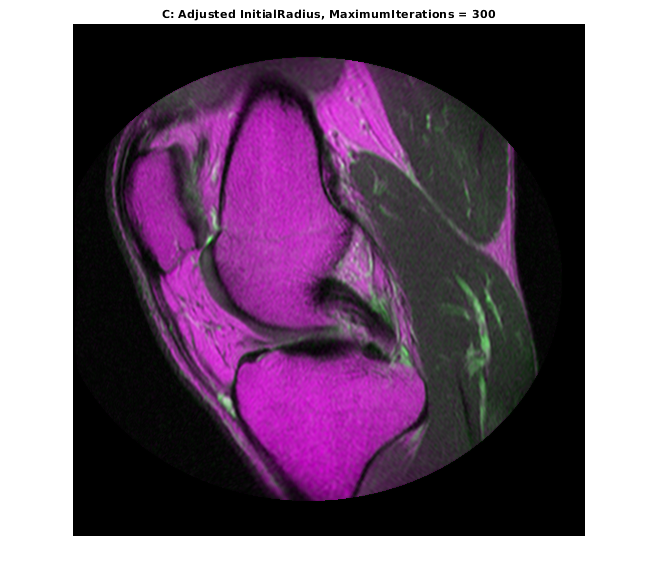

optimizer.MaximumIterations = 300; movingRegisteredAdjustedInitialRadius300 = imregister(moving,fixed,'affine',optimizer,metric); imshowpair(movingRegisteredAdjustedInitialRadius300,fixed) title('C: Adjusted InitialRadius, MaximumIterations = 300')

Дальнейшее совершенствование регистрации было достигнуто путем многократного использования InitialRadius оптимизатор, сходящий с предыдущей регистрации и позволяющий оптимизатор взять большое количество итераций.